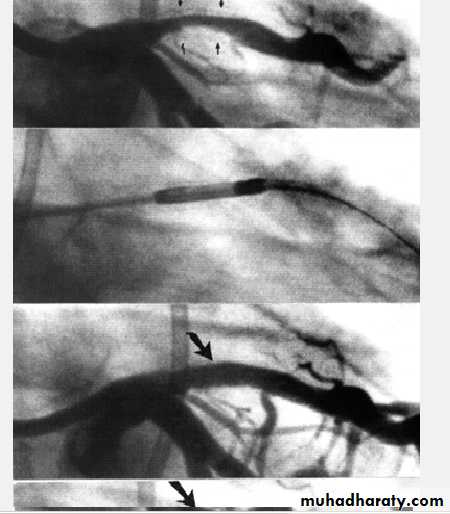

RevascularizationPercutanous C. Intervention (PCI) or C.A Bypass Grafting (CABG)

PCI which include Balloon Angioplasty + - Stenting Is indicated in discrete single vessel or two vessel lesions except that of the Proximal Left Anterior Descending artery LADCABG is for Left Main Stem lesion , Three Vessel Disease, and proximal LAD 1-2 vessels Disease

Especially diabetic pts and also those with LV dysfunction

Benefits and drawbacks of PCI

PCI benefitsImproves symptoms only (no evidence it improve survival ) and used for stenosis of native CA or graft .

PCI drawbacks ( related to lesion morphology, operator skills, and co morbidity ( page 588 Davidson)

1- Dissection and or Thrombosis ( 2-5%) Usually corrected by stenting

2- Restenosis occur in up to 33% in Angioplasty and reduced by Stenting with Bare Metal Stent ( BMS ) and reduced further by using Drug Eluting Stents (DES). Restenosis still occur in 10%. Dual antiplatelets needed

3- Late stent thrombosis occur in 0.6 % every yr.